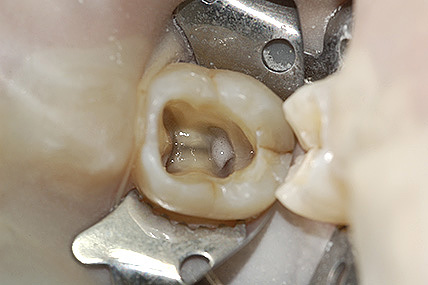

Si rimuove tutto il materiale presente all’interno dei canali; la rimozione di questo materiale si ottiene con dei solventi appositi coadiuvato dall’utilizzo di lime manuali o montati su manipoli ad ultrasuoni, successivamente si esegue una detersione e sagomatura dei canali radicolari per mezzo di irriganti disinfettanti quali l’ipoclorito di sodio (un potente battericida) spesso riscaldato per aumentarne la capacità antibatterica, con strumenti rotanti in nichel titanio azionati da appositi manipoli elettrici.

Dopo avere deterso e sagomato i canali radicolari si passa all’otturazione degli stessi con guttaperca calda e quindi al sigillo coronale (nuova otturazione o corona), fase finale che impedisce la re-infezione batterica dei canali stessi.